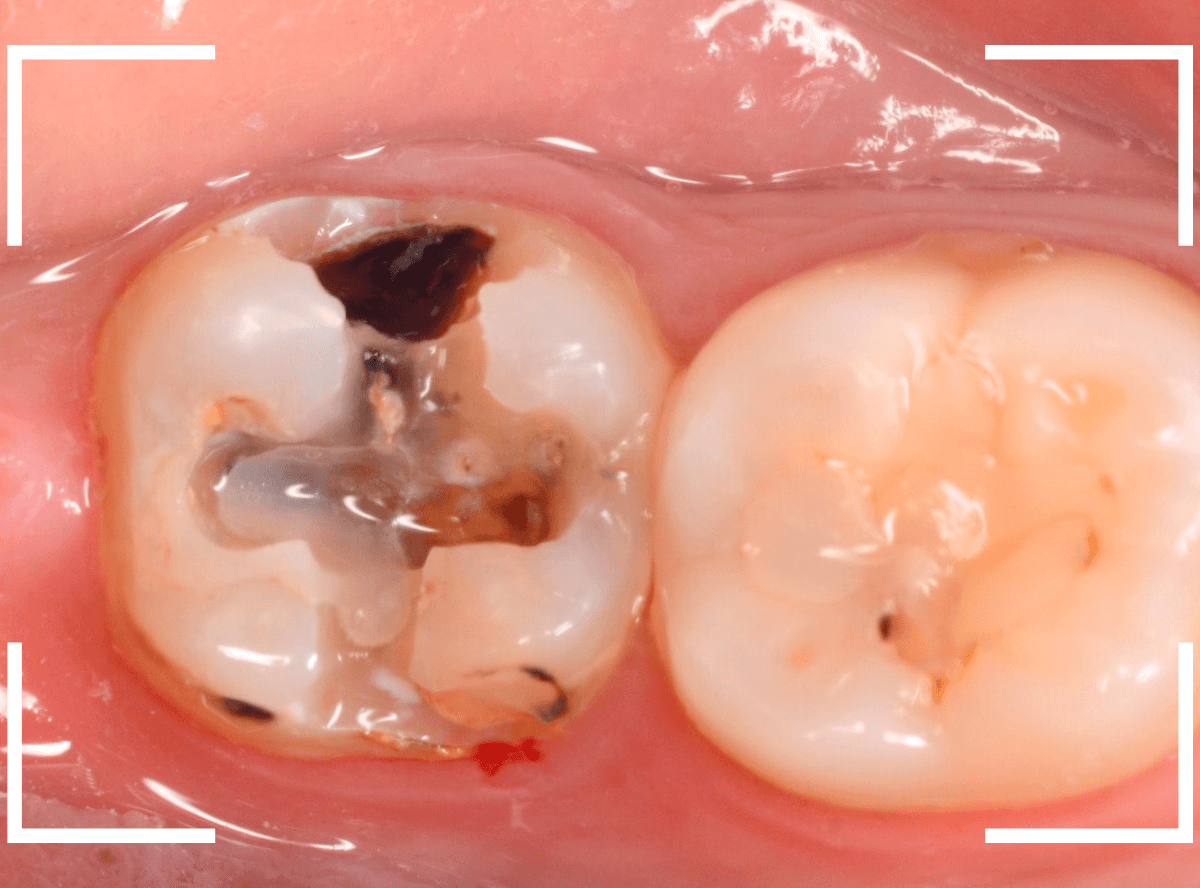

Case.12 金属のつめものの下の状況がわからない

定期メンテナンスに通っていらっしゃっている患者さんです。

金属のつめものが若干不適合気味になっているのと、その周りが黒くぼやっとなっていて怪しいですが、金属色が透けているのか虫歯になり始めてるのか、よくわかりません。

レントゲン写真で確認します。

虫歯があるのかはっきりしない写り方です。

患者さんに状況を説明の上、つめものを外して調べてみる事にしました。

つめものを外すと、虫歯が出てきました。

金属のつめものの下に、アマルガムという金属がつめてあるのも見られます。

あとは、少しずつ削りながら、虫歯を調べます。

全ての虫歯を除去しました。

幸い、あまり大きく歯を削らずに済みました。

早いうちに治療が出来てよかったかと思います。